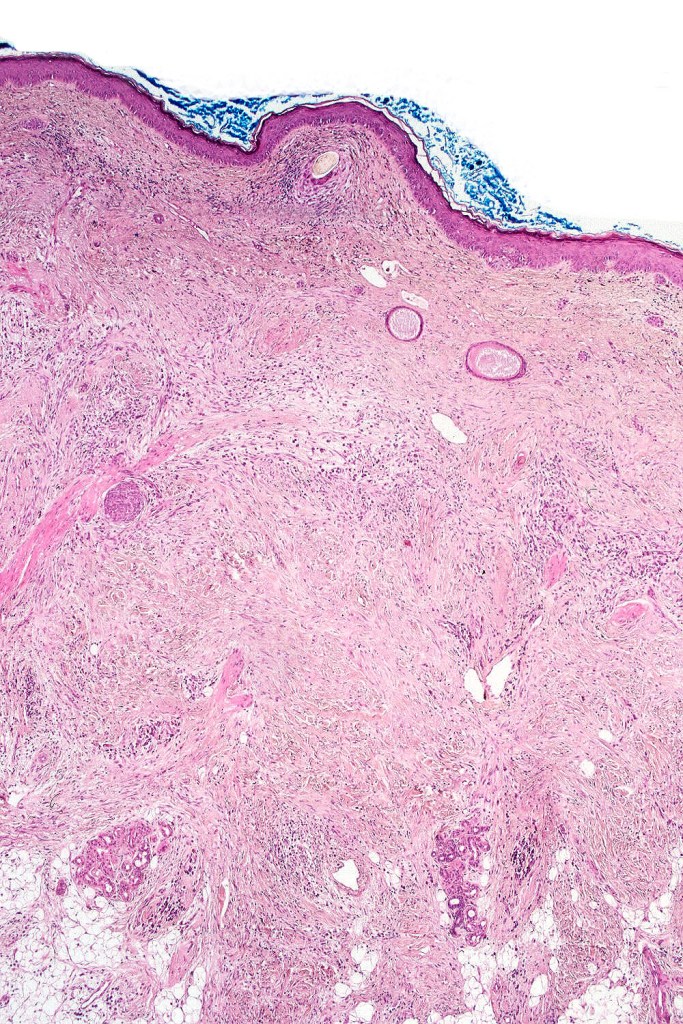

Histological features

•+/- Lentigo maligna (some examples are devoid of a junctional component)

•Paucicellular spindle cell infiltrate with “myxoid” fine to a dense collagenous stroma

•Hyperchromatic nuclei

•Variable pleomorphism

•Lymphoid aggregates*

•Neurotropism

•Neural transformation

•Mixed desmoplastic & spindle cell variant (10%)